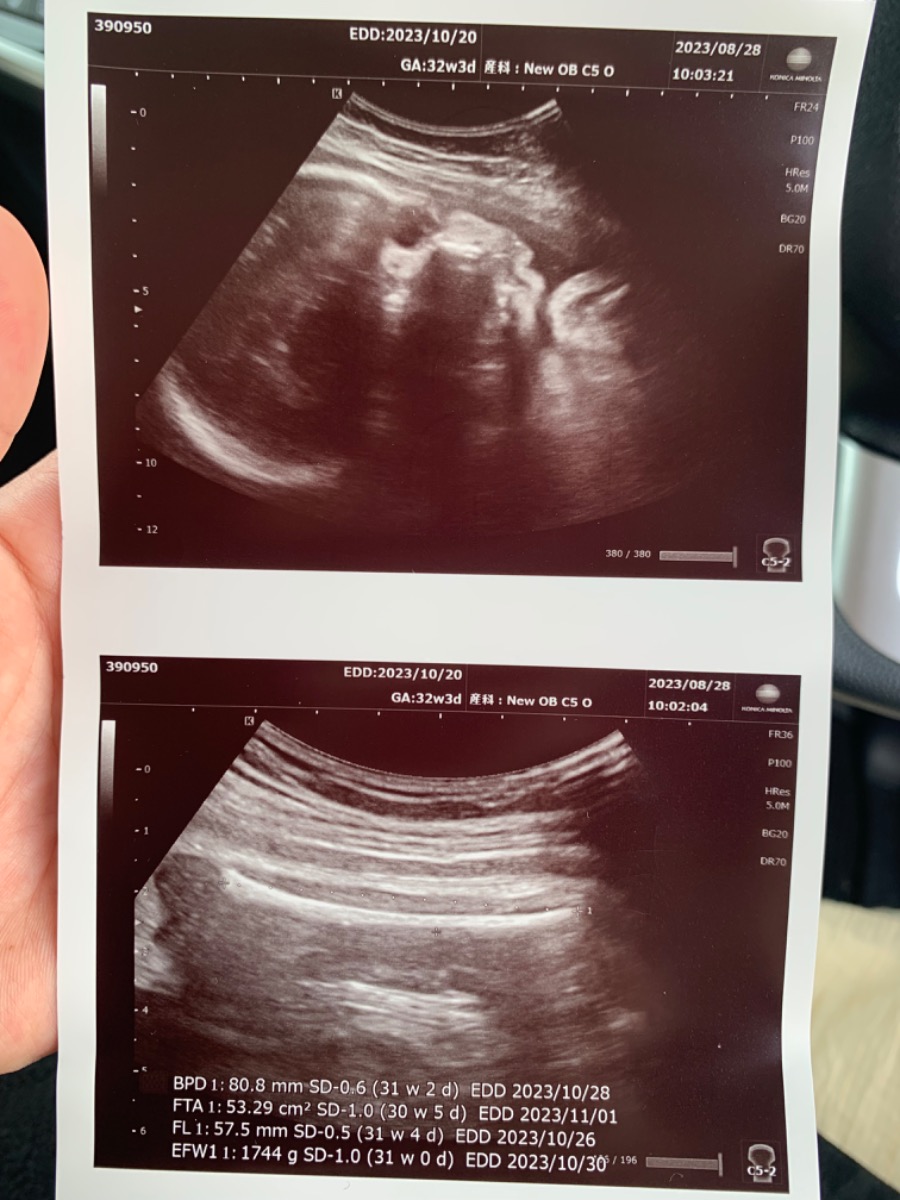

Bé con nhà e Hnay did khám ở Nhật 32w3d mới được 1744gr như hình thì liệu có bé quá k ạ ! Với trong tuần này bé con nhà e đầu vẫn nằm trên và nghiêng bên phải thì liệu ít tuần nữa có dễ quay đầu thuận ngôi để sinh thường k ạ ! Khám ở bên Nhật cũng hơi lo lắng 1 xíu ạ ! Admin tư vấn giúp e !